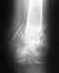

Re: Перелом голени со смещением отломков

Хорошо, спасибо. А меня еще вот такой вопрос волнует, если все правильно сделают, я не буду хромать? И как быстро я смогу приступить к полноценой жизни?

Причин для хромоты не будет. После снятия швов можно возвращаться к обычной жизни.